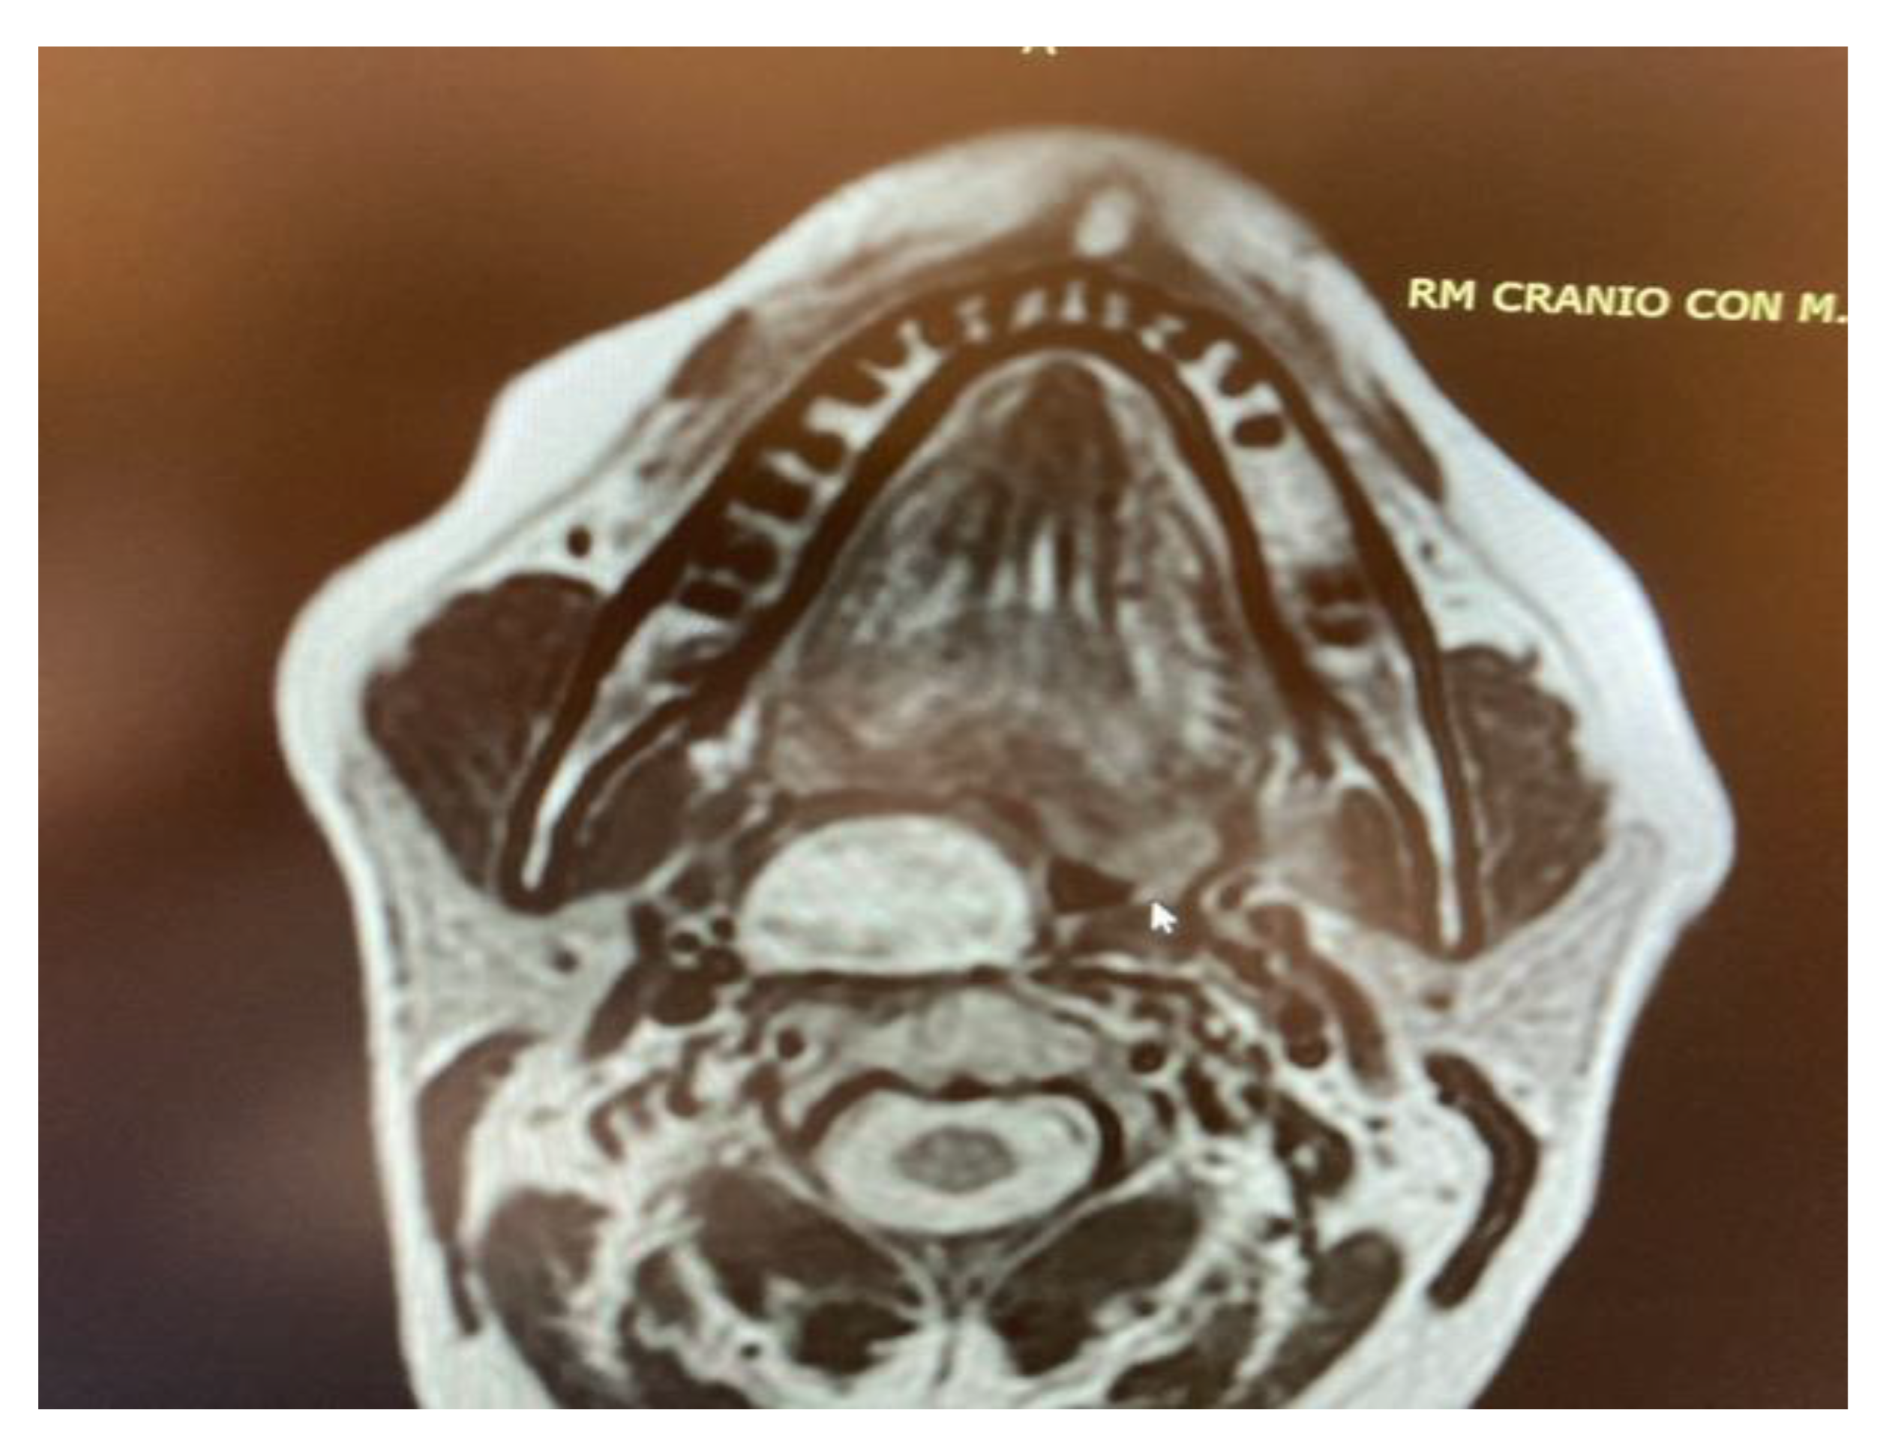

- Five pleomorphic adenomas that arose from minor salivary glands in three cases and from the deep lobe of the parotid gland in two cases. All of these tumours were situated in the true PPS, medially with respect to the great vessels. In all the patients, no complications were observed during and after surgery. Hospitalisation time was two days for three patients, three days for one patient and four days for the other patient. No tumour recurrence was observed after sixteen, nine, eight and seven years for the first four patients. Evaluating the recurrence in the last patient is still not possible due to the short follow-up period, since the patient underwent surgery in 2021.

- One lipoma arose from the true parapharyngeal space. The patient underwent surgery in 2012 and had no intraoperative and no postoperative complications. No recurrence was observed after ten years. The hospitalisation time was two days.

- One ectopic thyroid arose from the right true parapharyngeal space. This was the only case in which a fine needle aspiration citology (FNAC) was performed, and the results were inconclusive. The patient underwent surgery in 2003 with no intraoperative or postoperative complications. The hospitalisation time was three days. No recurrence observed after eighteen years.

- Two schwannomas (Figure 5) originating from the cervical sympathetic chain and that arose in the superomedial aspect of the PPS, medially to the carotid sheath. The first patient underwent surgery in 2008, the second in 2019. No complications were observed during surgery and no tumour recurrence has been observed after 14 and 4 years, respectively. The only long-term complication observed was Horner syndrome (Figure 6), despite the continuity of the nerve not being interrupted. The hospitalisation time was three days for both patients.